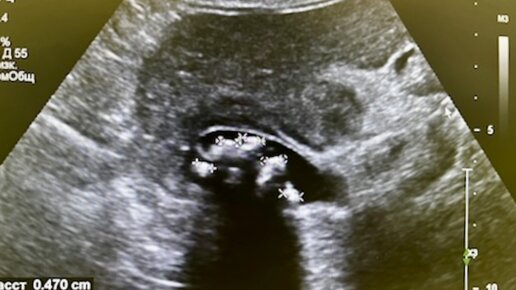

В настоящее время интерес к растворению камней в желчном пузыре заметно возрос. Однако, научные исследования указывают на ограниченные возможности лечения желчнокаменной болезни без операции, а также наличие многочисленных противопоказаний. Чтобы получить медицинский взгляд на методы растворения желчных камней, рекомендую изучить данную статью. Желчнокаменная болезнь (ЖКБ) – это заболевание, характеризующееся образованием камней в желчном пузыре и желчных путях, встречается у 10-15% населения и может протекать как с обилием разных жалоб и осложнений, так и бессимптомно...

В настоящее время значительно вырос интерес к растворению камней в желчном пузыре. По данным научных исследований показания к лечению желчнокаменной болезни без операции с помощью растворения камней довольно ограничены, также имеется большое количество противопоказаний. Чтобы узнать медицинский взгляд на то, какие же существуют возможности для растворения желчных камней, рекомендуем прочитать данную статью. Общая информация Желчнокаменная болезнь (ЖКБ) – заболевание, сопровождающееся образованием...